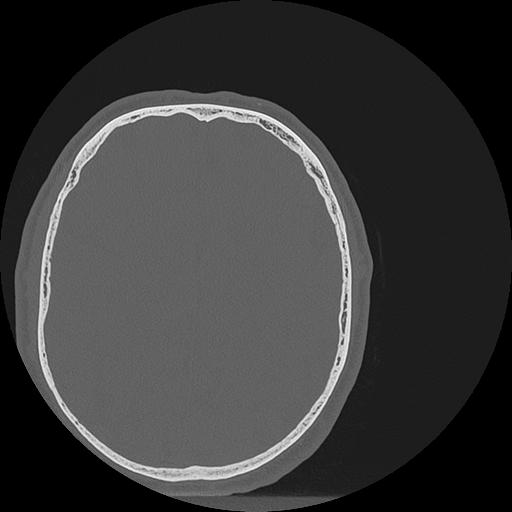

7 HUESO,,Vol,0.5,HUESO,,